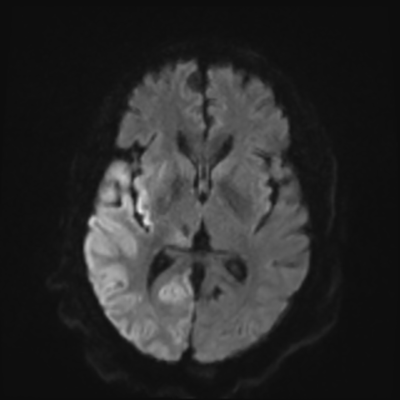

You come back the next day and see how things are going. The patient's electrographic record has shown a moderate encephalopathy (diffuse slowing, disorganization) with frequent right posterior quadrant delta slowing. Based on this result, and an adequately improved clinical examination, you give the okay to proceed with obtaining an MRI of his brain. This is shown below.

MRI brain (DWI)